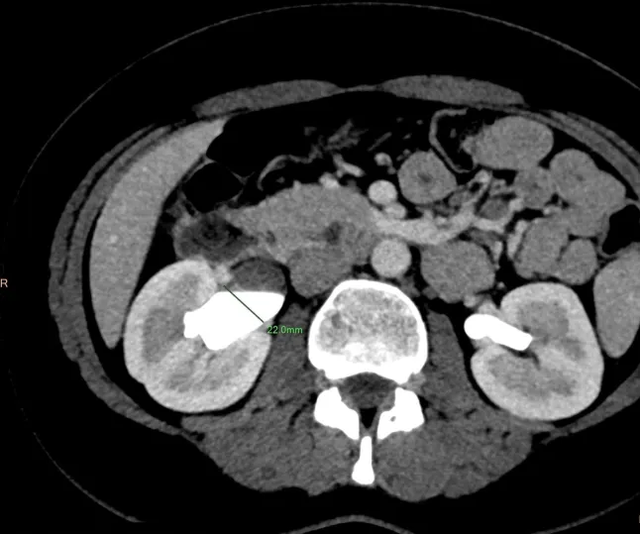

Bởi vì khi tới bệnh viện, Sarah cũng chỉ cho rằng mình bị sỏi thận tái phát. Nhưng kết quả chụp cắt lớp tiết niệu khiến các bác sĩ bất ngờ: thận phải và niệu quản của cô bị sưng đáng kể, với đường kính giãn nở lên đến 22mm. Nguyên nhân được xác định là do cốc nguyệt san đặt sai vị trí, vô tình chặn đường lưu thông của nước tiểu. Điều này dẫn đến hiện tượng ứ nước thận, gây nhiễm trùng và đau đớn kéo dài.